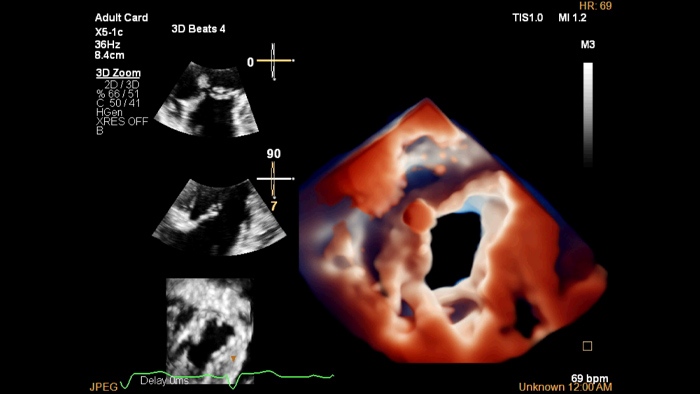

革新的なX5-1c経胸壁トランスジューサと、強力なnSIGHT Plusアーキテクチャにより実現される、高いイメージパフォーマンスを実感していただけます。

X5-1c TV TrueVue

TrueVue

TrueVueと仮想光源により、欠損部位や構造の奥行きの把握が容易になり、経胸壁および経食道エコーによる観察力が向上します。